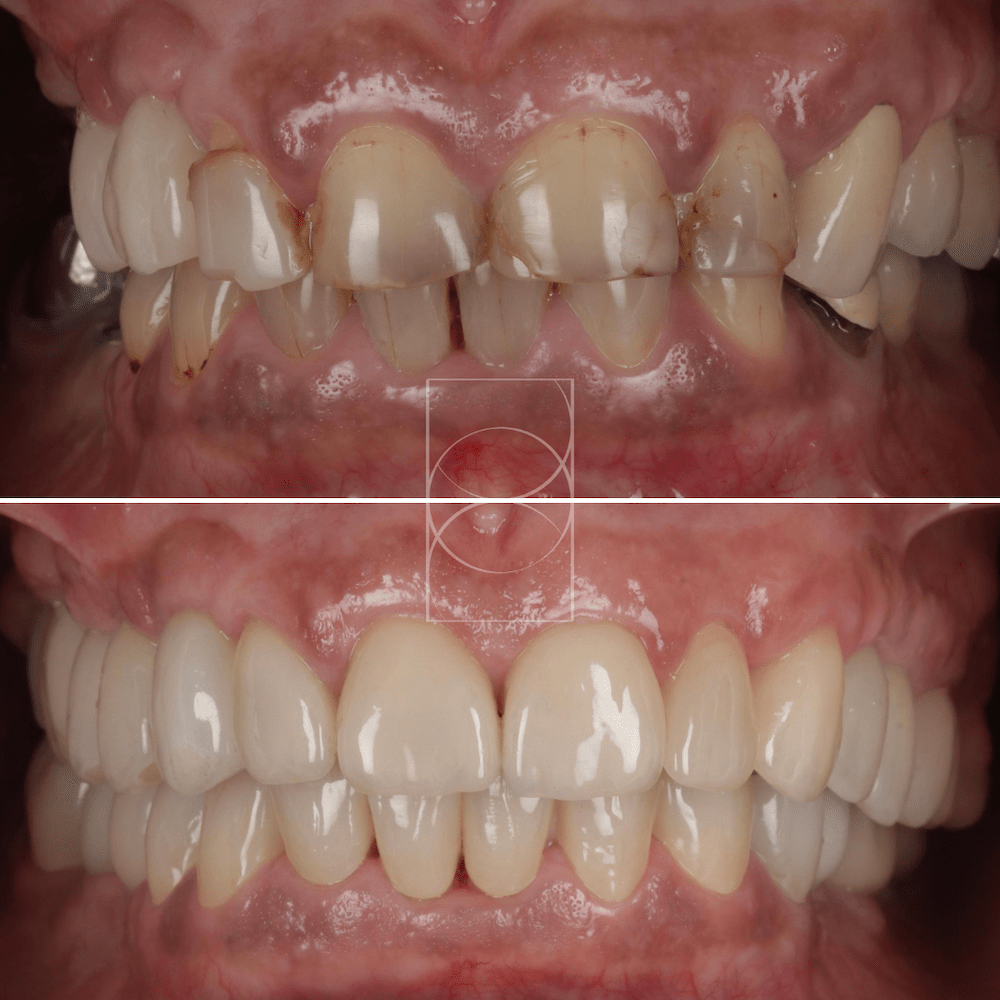

Avant/après d’un traitement restaurateur de l’usure d’un de nos patients

Une réhabilitation d’une, voire des deux, arcades dentaires est souvent nécessaire pour préserver la fonction, prévenir les dommages supplémentaires et restaurer un sourire harmonieux.

Le traitement de l’usure dentaire à l’aide de céramiques collées est une solution durable et esthétique, particulièrement privilégiée pour les dents usées. Les céramiques sont des matériaux extrêmement résistants et biocompatibles, conçus pour imiter parfaitement l’aspect et la fonction des dents naturelles.

Ce traitement consiste à coller des facettes, des onlays ou des couronnes en céramique sur les dents usées, après une préparation minimale pour préserver un maximum de tissu dentaire sain. Grâce à leur solidité et leur stabilité, ces restaurations sont idéales pour redonner un sourire fonctionnel et harmonieux tout en protégeant les dents contre de futures dégradations.